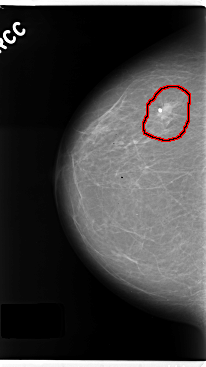

C_0190_1.RIGHT_CC

RIGHT_CC LINES 4760 PIXELS_PER_LINE 2672 BITS_PER_PIXEL 12 RESOLUTION 50 OVERLAY

FILE: C_0190_1.RIGHT_CC.OVERLAY

TOTAL_ABNORMALITIES 1

ABNORMALITY 1

LESION_TYPE CALCIFICATION TYPE ROUND_AND_REGULAR DISTRIBUTION CLUSTERED

LESION_TYPE MASS SHAPE OVAL MARGINS SPICULATED

ASSESSMENT 5

SUBTLETY 5

PATHOLOGY MALIGNANT

TOTAL_OUTLINES 1

BOUNDARY